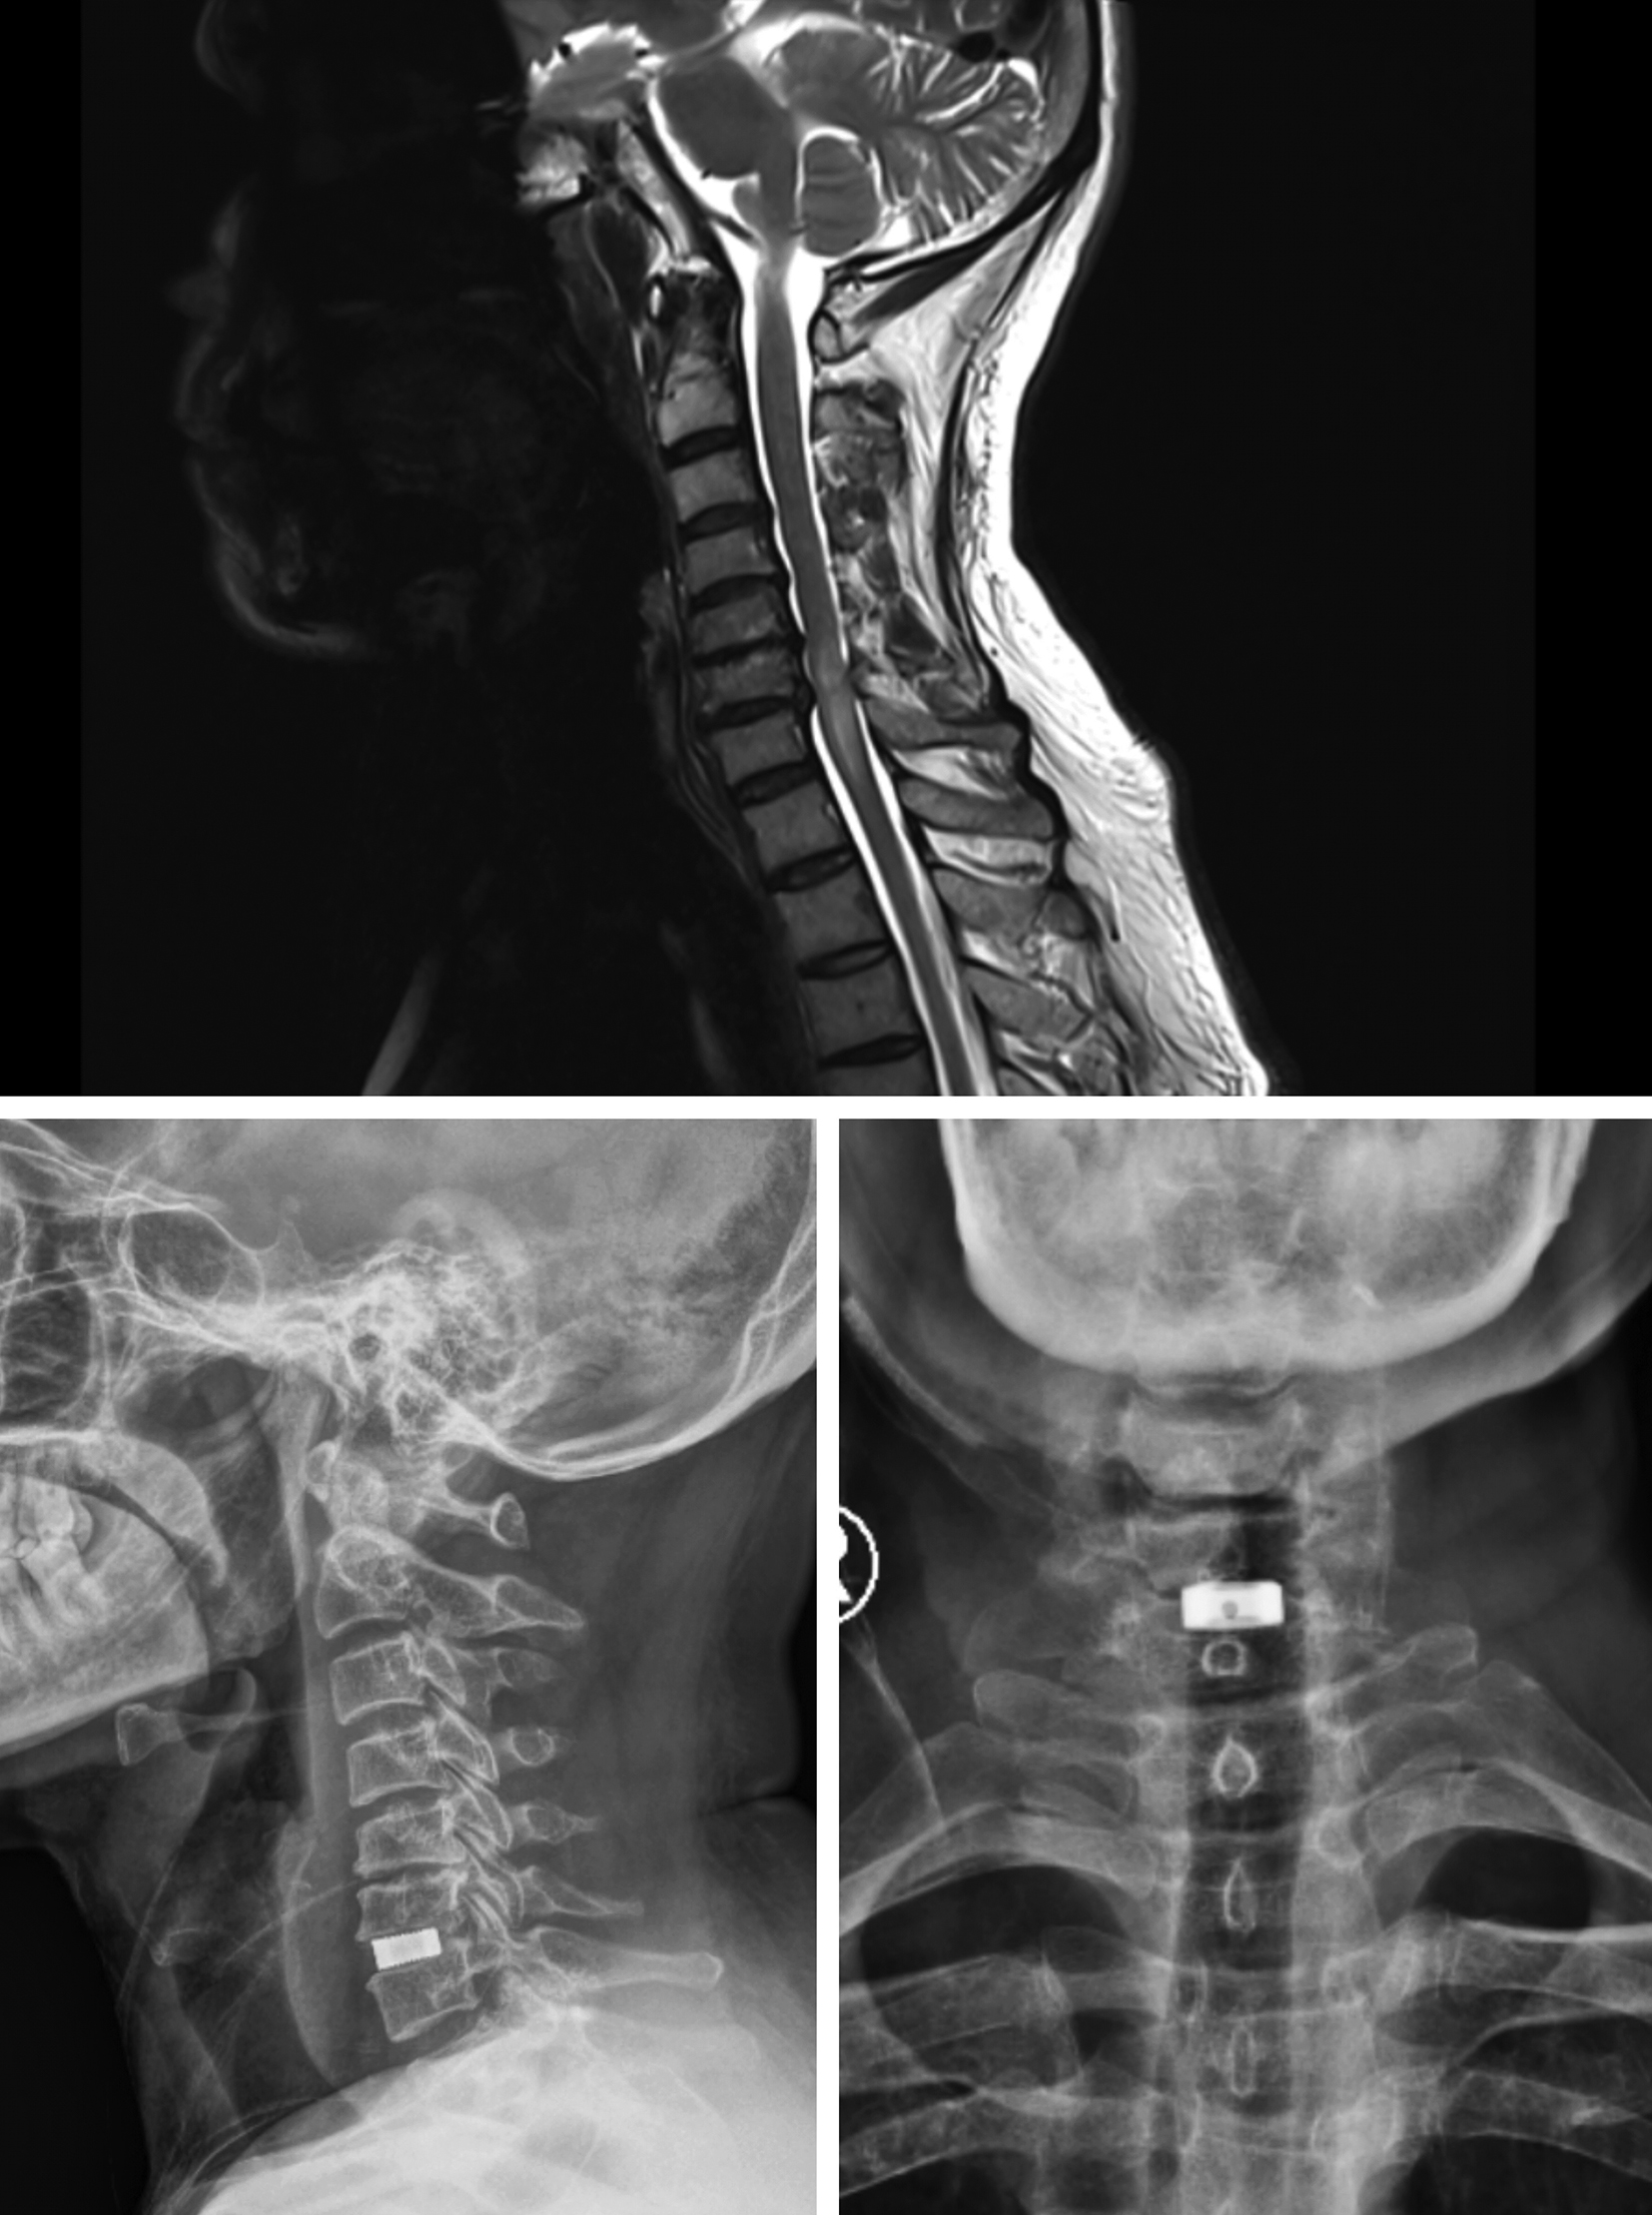

Figures 1-4 show pre-operative and post-operative radiological images in few of our patients.

Figure 2. A - Preoperative magnetic resonance imaging study of the cervical spine (T2 weighted image, sagittal view) showing cervical compressive myelopathy with disc osteophyte complex; B - Postoperative radiographic imaging study of the cervical spine (sagittal view) showing the cage in situ; C - Postoperative radiographic imaging study of the cervical spine (coronal view) showing the cage in situ